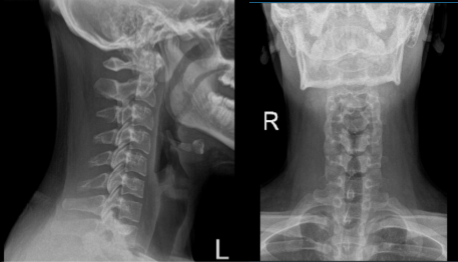

X Ray of Spine and left shoulder were presented during the visit, cervical spine X-ray showed an abnormal straightening cervical curve however left shoulder showed normal radiographs. In this follow up, I advised the patient to continue taking ibuprofen and an MRI will be presented the following week.

Cervical Spine X-ray 2 Views